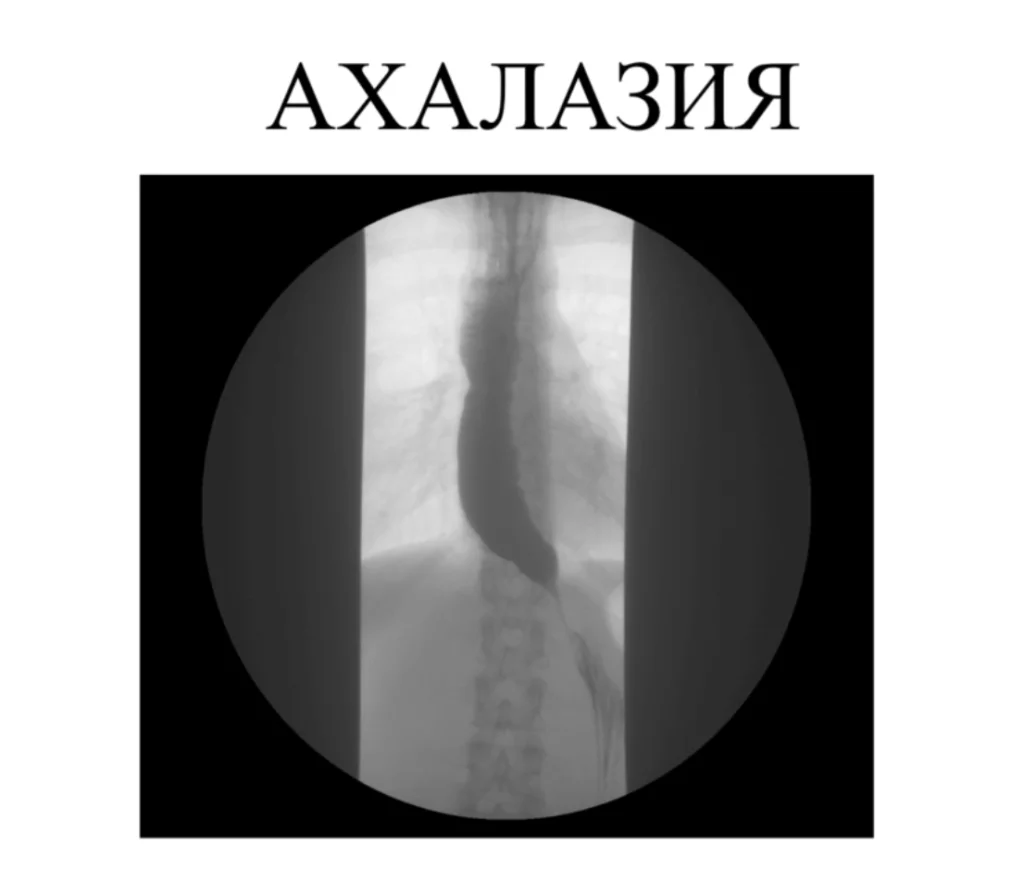

Ахалазия при синдроме Оллгрова

Для того, чтобы найти третью составляющую синдрома была выполнена рентгеноскопия с барием и фиброгастродуоденоскопия.

По результатам исследований была диагностирована ахалазия кардия второй степени и рекомендовано выполнение оперативного лечения.